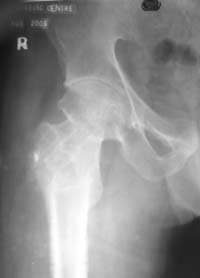

Виктор П. Волошин 15 Октябрь 2005, 21:47

Если есть опыт межвертельной остеотомии, то лучше не придумаешь, иначе остается высокая вероятность несращения. При такой Ртг картинке после операции мы ни разу не наблюдали АНГБК, даже если открывали перелом спереди для хорошей ориентации.

ВВП, МОНИКИ